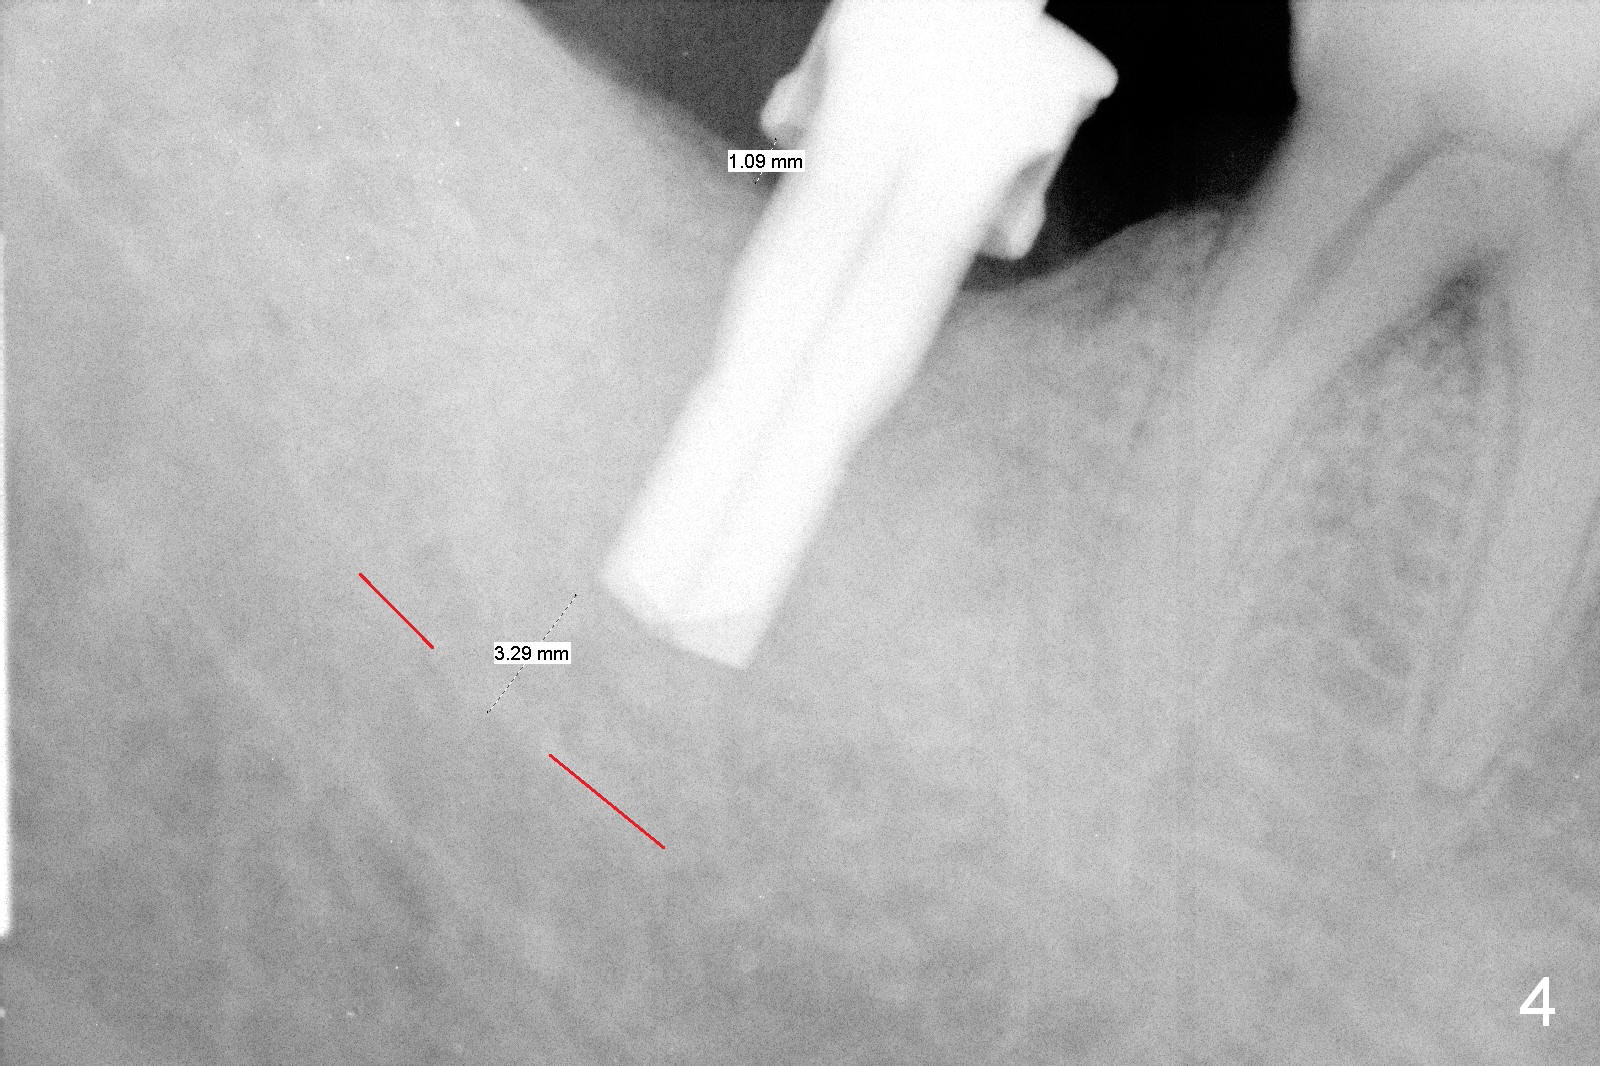

The 61-year-old man is nervous about dentistry. When he returns for #4 implant, he wants an implant at #31 first. Fig.1 shows #31 crown fracture after root canal therapy. Three years after crown placement, there is sign of mesial root fracture (Fig.2 arrowheads). Four years post extraction, bone height is 12 mm (Fig.3 parallel pin 10 mm). An extra wide implant is to be placed, since there is enough bone width. With infiltration anesthesia, the patient feels pain when a 5.4x10 mm drill is being used, 1 mm short of the desirable depth (Fig.4). After Inferior Alveolar Nerve block, the last drill reaches the depth. A 5.9x10 mm implant is placed with insertion torque 50 Ncm (Fig.5 I). A 7.8x4(3) mm cemented abutment (A) is placed immediately. After suturing, the restorative portion of the abutment is covered by the gingiva. It is probably due to over tightening the sutures. It would be ideal to adjust the gingival level before tightening the second suture.